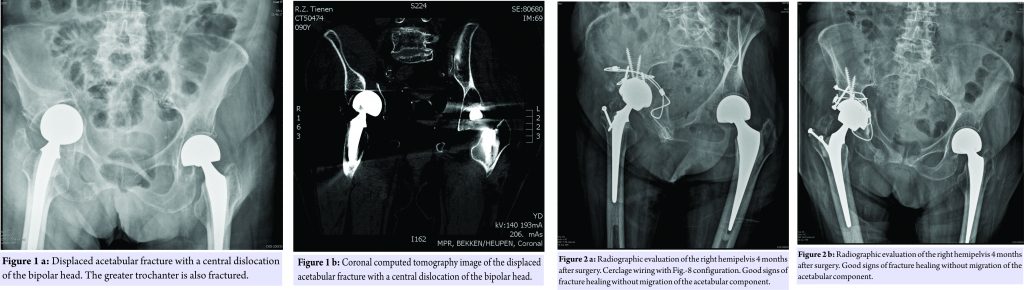

A 90-years-old female was transferred to the hospital after sustaining a low-energy trauma, a simple fall. She experienced pain at the right hip and pelvis. Weight bearing on the affected side was no longer possible. The medical file revealed a hemiarthroplasty for a displaced femoral neck fracture at the right and left side, respectively 6 and 8 years ago. She was ambulating only short distances using a walking stick. Radiographic assessment revealed a displaced acetabular fracture with a central dislocation of the bipolar head. Impaction against the acetabular roof resulted in a displaced fracture of the greater trochanter (Fig.1a and 1b).

No other bony lesions or associated neurovascular injuries where noted. After a careful preoperative assessment, the surgical plan consisted of a stabilization of the acetabulum fracture by means of cerclage wires together with a conversion of the hemiarthroplasty to a total hip prosthesis. The patient was positioned in a lateral decubitus. A tri-radiate approach was preferred to gain a wide exposure to the hip joint. The greater trochanter was already fractured. So, no osteotomy at that level needed to be done. After removal of the bipolar head, the femoral component seemed to be fixed very well and was left in place. First of all, a 2mm braided cable (Zimmer, Inc., Warsaw, Indiana) passed around the body of the ischial bone using Statinsky aortic clamps. Thereafter, one end of the wire carefully passed along the inner pelvic surface while the other passed under beneath the sacrospinal ligament. Both ends were clamped together above the acetabulum, creating a figure-8 configuration (Fig. 2a) as described by Mears et al [4]. A second cerclage wire was used to fix the posterior column (Fig. 2a). After reduction and stabilization of the acetabular fracture, the acetabulum was progressively reamed to the appropriate size. A cementless Trabecular Metal cup (Zimmer, Inc., Warsaw, Indiana) was inserted and titanium screws were applied to provide additional stability to the construct. A highly crosslinked polyethylene liner was implanted together with a new metallic femoral head. The fracture of the greater trochanter was reduced and fixed by means of two AO screws. Finally, a reduction of the total hip prosthesis was performed which seemed to be stable without major leg length discrepancy. Postoperatively, continuous passive motion of the operated hip was started immediately. Weight bearing was not allowed during the first 6 weeks. Thereafter, ambulating using a walking device and partial weight bearing (20kg) was allowed. Four months after surgery, she regained her pre-operative functional status and a radiographic evaluation of the right hemipelvis showed good signs of the fracture healing without migration of the acetabular component (Fig. 2a and 2b).